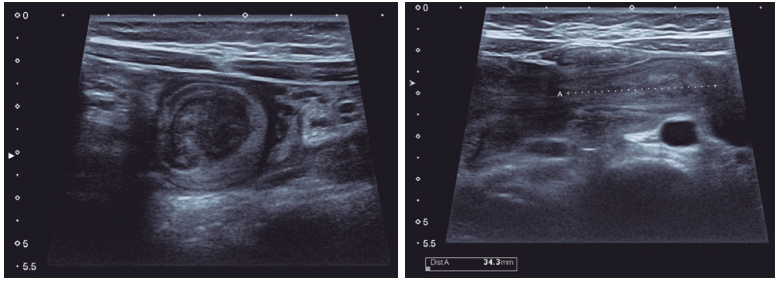

Varón de 5 años de edad, que presentó cuadro clínico de tres semanas de evolución, caracterizado por dolor abdominal de tipo cólico, a predominio periumbilical y en el flanco derecho, asociado a vómitos ocasionales durante el lapso de evolución. Consultó en el centro asistencial, donde se observó al momento de la valoración física, abdomen blando, doloroso a la palpación profunda, asociado a masa palpable en hemiabdomen derecho, sin signos francos de irritación peritoneal. Se le realizó una ecografía abdominal, que evidenció a nivel del hipocondrio y flanco derecho una imagen redondeada, con centro ecogénico, y dos anillos hipoecogénico e hiperecogénico periféricos (Figuras 1 y 2).

Figuras 1 y 2. Ecografía abdominal en cortes transversales y longitudinales.